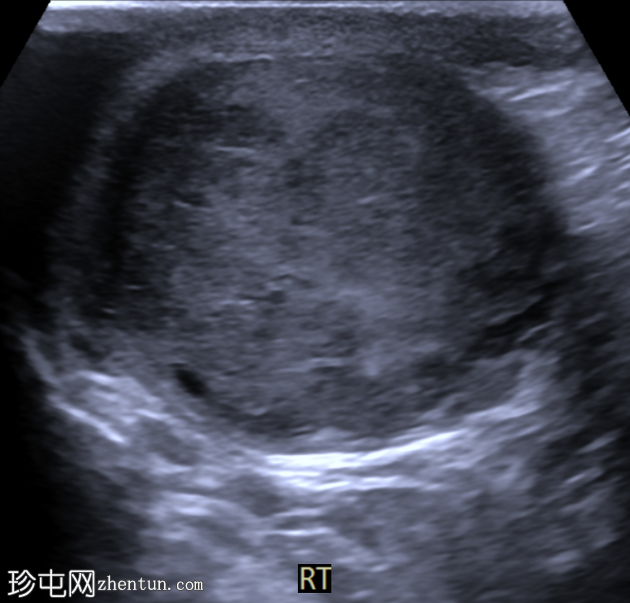

右侧睾丸内可见一大小约3.0 x 5.0 cm的异质性分叶状低回声肿块。肿块内未见囊性区域或钙化。彩色多普勒超声检查显示肿块内血流丰富。左侧睾丸正常。